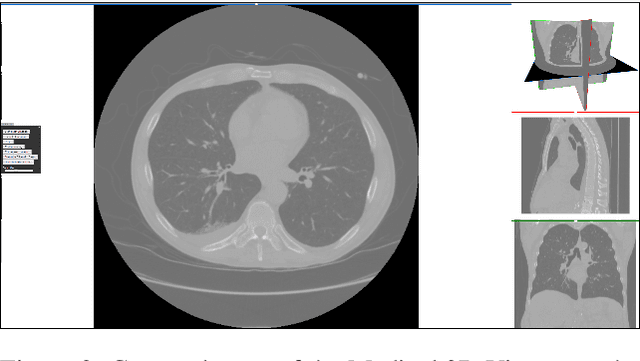

Abstract:Medical imaging is an important tool for the diagnosis and the evaluation of an aortic dissection (AD); a serious condition of the aorta, which could lead to a life-threatening aortic rupture. AD patients need life-long medical monitoring of the aortic enlargement and of the disease progression, subsequent to the diagnosis of the aortic dissection. Since there is a lack of 'healthy-dissected' image pairs from medical studies, the application of inpainting techniques offers an alternative source for generating them by doing a virtual regression from dissected aortae to healthy aortae; an indirect way to study the origin of the disease. The proposed inpainting tool combines a neural network, which was trained on the task of inpainting aortic dissections, with an easy-to-use user interface. To achieve this goal, the inpainting tool has been integrated within the 3D medical image viewer of StudierFenster (www.studierfenster.at). By designing the tool as a web application, we simplify the usage of the neural network and reduce the initial learning curve.